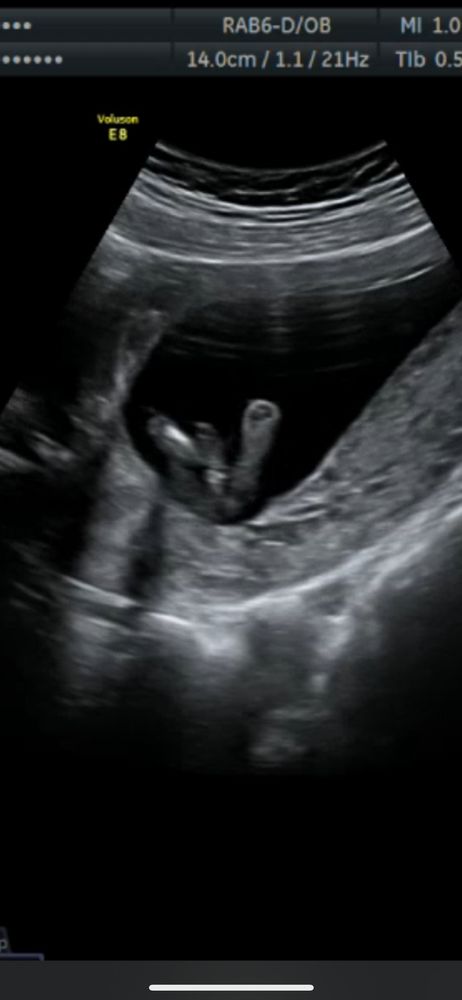

Мальчик или девочка

между ног пуповина, как на первом так и на втором фото, так что можно и ошибиться

Изображение Вот здесь будто что-то виднеется

Мальчик

Тоже кажется, что мальчик, как будто бугорок есть

Виктория, мне тоже кажется, что мальчик

Больше на пуповину похоже